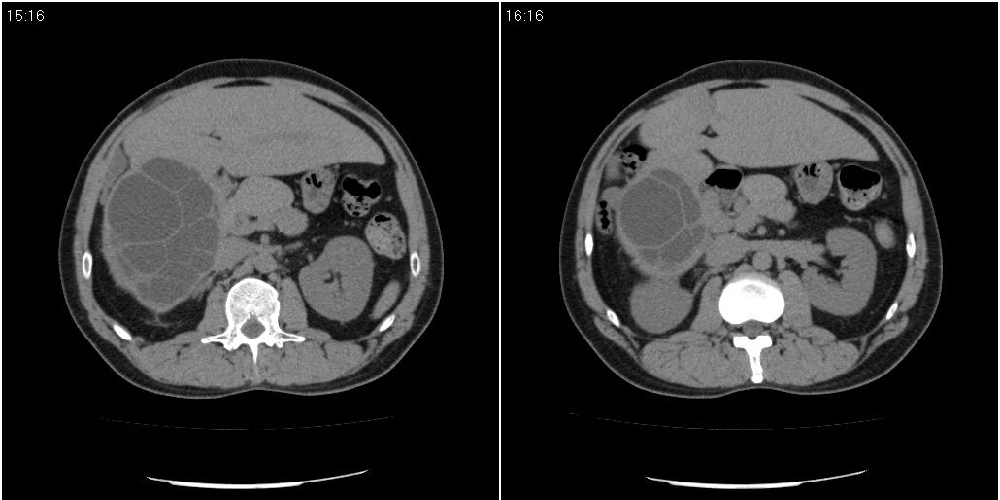

该患者70岁男性,手术后10年,现复查。2008年6月份本人曾经发过一极其类似的病例,只是部位略有差异。

肝脏多房性包虫囊肿

水上浮莲征,肝包虫囊肿。

肝脏及右侧胸腔包虫病。

大囊套小囊!肝脏多房性包虫囊肿